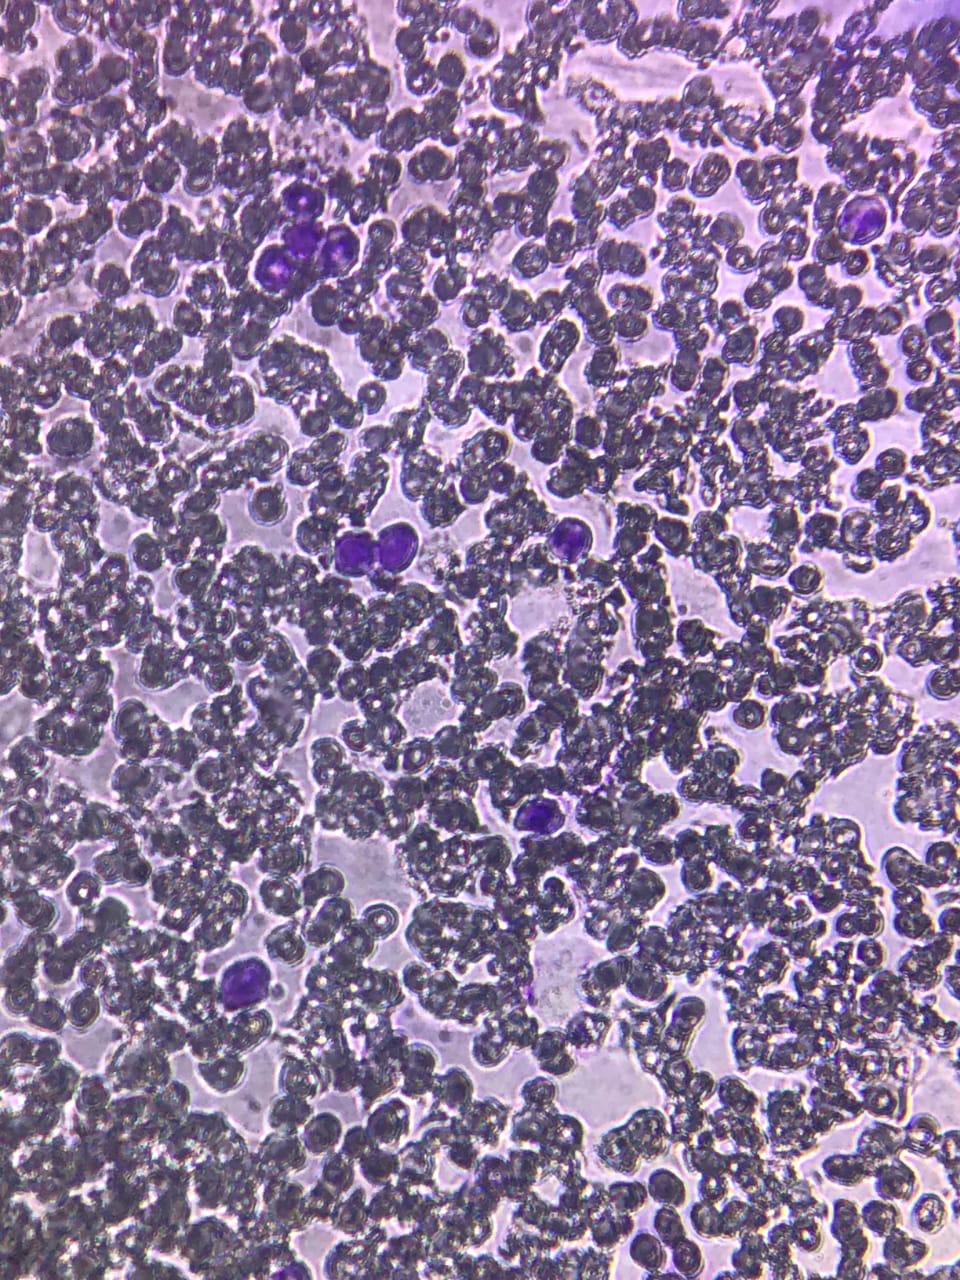

In a longitudinal strip of the film, students counted the various kinds of white blood corpuscles from top to the bottom. They counted 100 white corpuscles and noted it on a paper each type of white blood corpuscles encountered and calculated the percentage.

Detailed morphological and anatomical structures were observed by the students under a compound microscope and the outlined aims, objectives as well as outcomes were achieved.

![]() Slide preparation by the students | ![]() DLC slide under microscope showing different types of Leucocytes |

![]() Different types of Leucocyte seen in the side under Microscope | ![]() Dr. A. R. Rajoria, explaining the different Leucocytes present in the prepared slide |